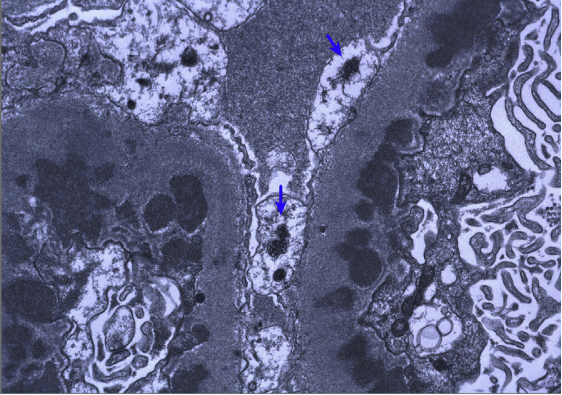

狼疮型肾炎Ⅴ型(膜性LN),大量上皮下电子致密物沉积,内皮细胞胞浆内可见管网状包涵体(蓝色箭头)(电镜)

狼疮型肾炎Ⅴ型(膜性LN),大量上皮下电子致密物沉积,内皮细胞胞浆内可见管网状包涵体(蓝色箭头)(电镜)